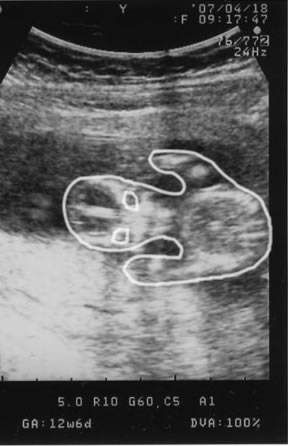

エコー写真を持って帰ってきた嫁。

嫁  「んー、やっぱ親子だわ・・・」

オイラ「んっ?何が」

うわっ!

一緒の寝姿に爆笑!!

でも、ちょっと羨ましいぜ・・・くそっ!